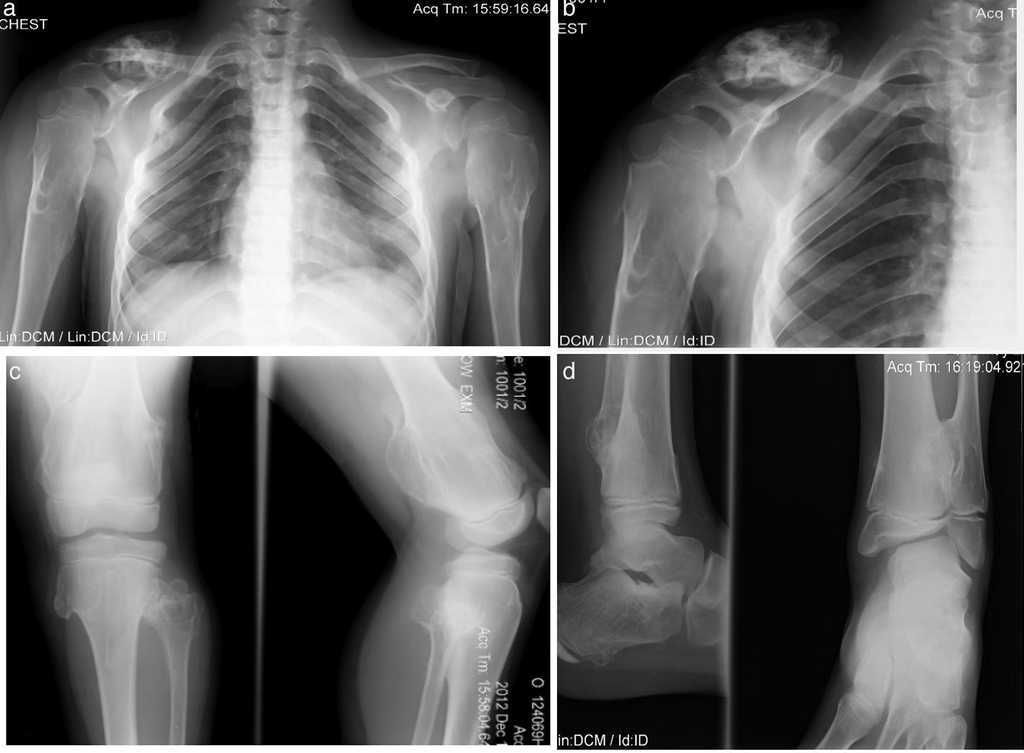

Paciente de sexo masculino de 8 años de edad con diagnóstico de hipotiroidismo subclínico desde los 8 meses hasta los 2.5 años, que se pudo normalizar. Se estableció el diagnóstico de OMH a los 2 años de edad, con lesiones en húmeros y muñecas. Su crecimiento ha sido satisfactorio, sin acortamiento de miembros inferiores, con peso y talla en el P50. Solo ha presentado disminución del arco de movimiento en muñecas y hombros y dolor ocasional en algunos movimientos articulares (Fig. 4).

Figura 4 Caso 3 (III2). Paciente masculino de 8 años que presenta lesiones osteocartilaginosas con patrón heterogéneo de predominio radiolúcido en región clavicular derecha (a), exostosis en submetafisiarias en región proximal de húmero derecho (b), tercio distal de fémures (c), porciones proximal y distal de tibia y peroné (c, d). Hay deformidad con ensanchamiento medular en húmeros y fémures, principalmente. Las regiones fisiarias no están comprometidas.